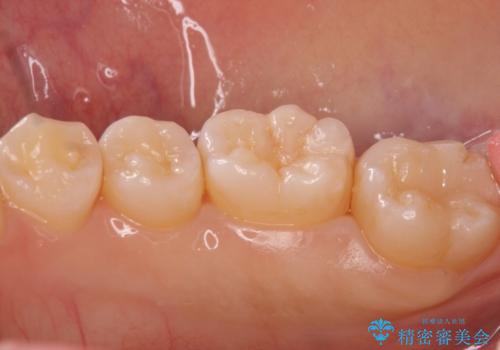

奥歯の黒ずみが気になる セラミックインレーでの治療

- 奥歯の黒ずみが気になるとのことで来院されました。

樹脂での治療も考えましたが、材料の劣化を避けるためにセラミックインレーでの治療をすることとなりました。

- 右下7 セラミックインレー 77,000円費用は治療当時の料金となります

セラミックは樹脂が含まれていないため劣化の面では非常に優れた材料です。